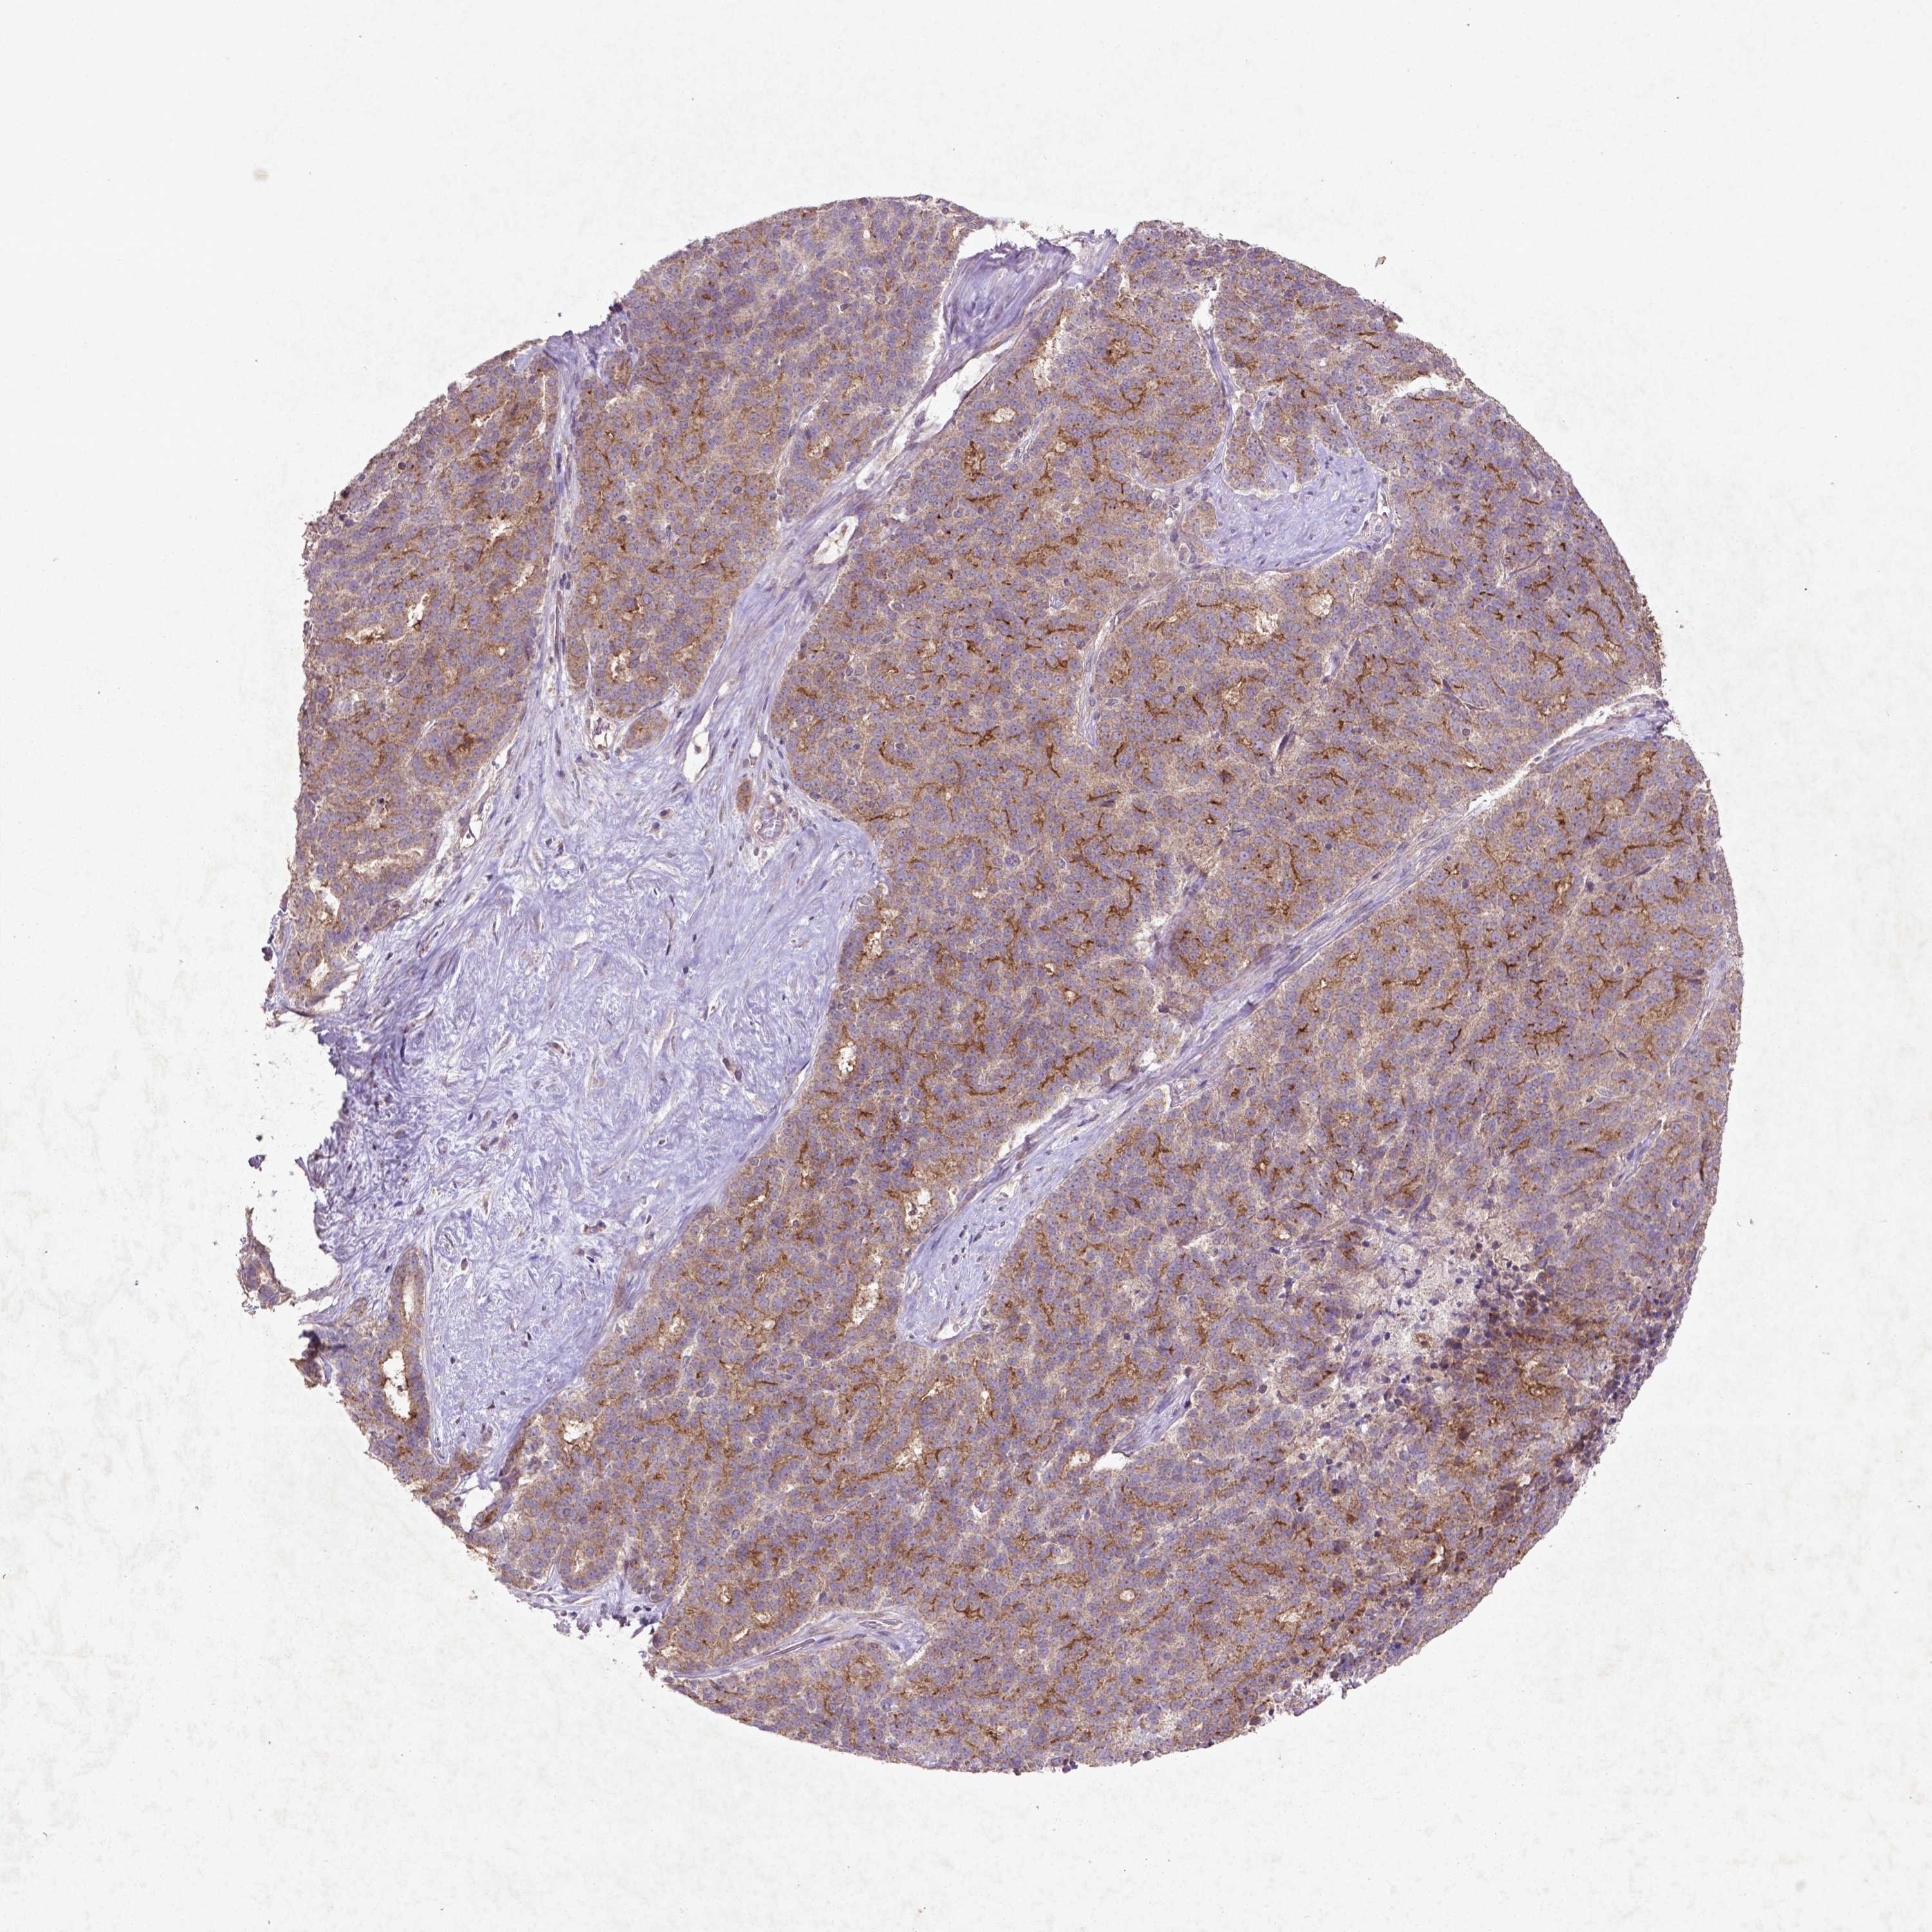

LIVER CANCER - Protein expressioni

A mouse-over function shows sample information and annotation data. Click on an image to view it in a full screen mode. Samples can be filtered based on level of antibody staining by selecting one or several of the following categories: high, medium, low and not detected. The assay and annotation is described here.

Note that samples used for immunohistochemistry by the Human Protein Atlas do not correspond to samples in the TCGA dataset.

Antibody stainingi

Antibody staining in the annotated cell types in the current human tissue is reported as not detected, low, medium, or high, based on conventional immunohistochemistry profiling in selected tissues. This score is based on the combination of the staining intensity and fraction of stained cells.

Each image is clickable and will lead to virtual microscopy that enables deeper exploration of all samples and also displays staining intensity scores, fraction scores and subcellular localization as well as patient and tissue information for each sample.

Carcinoma, Hepatocellular, NOS

Cholangiocarcinoma